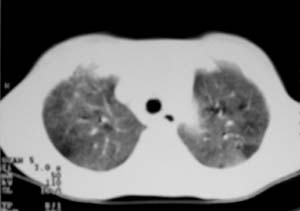

以下是引用zjzjr在2007-9-20 12:29:00的发言:[br]双肺磨玻璃改变,考虑肺水肿.

以下是引用yangzongshan在2007-9-20 18:29:00的发言:[br]两肺毛玻璃样改变,其内可见肺纹理影,无胸腔积液,故考虑肺泡蛋白沉积症

以下是引用276894491在2007-9-20 13:40:00的发言:[br]考虑肺水肿;外源性过敏性肺炎不排除。

以下是引用逸风在2007-9-20 20:45:00的发言:[br]两肺磨玻璃样改变,临床病史短,发热,考虑病毒感染合并右肺代偿性肺气肿.待排肺水肿,病史短,不支持肺泡蛋白沉着症.